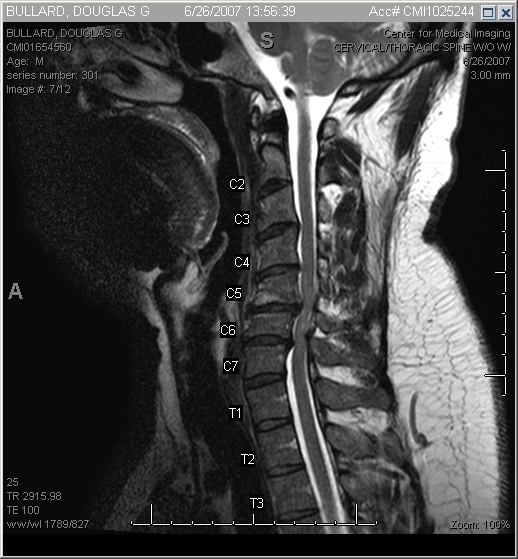

The end result - artifical discs. The old discs have been removed, the offending bits of bone removed, and the new joints inserted.

Don't ask me why my neck's tilted like that - it's exactly the way the radiologist positioned my head for the shot.